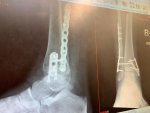

Three months since my accident and my bones have now healed!

Ligaments are going to take up to a year but that’s fine.

Consultant was very pleased and has given me the go ahead to ditch the boot! And drive!

The syndo screw (through bones) will likely snap at some point so he told me not to be alarmed if I hear a loud pop and get pain for 2-3 weeks (glad he warned me!) but usually they still just leave it in even if it’s broken.